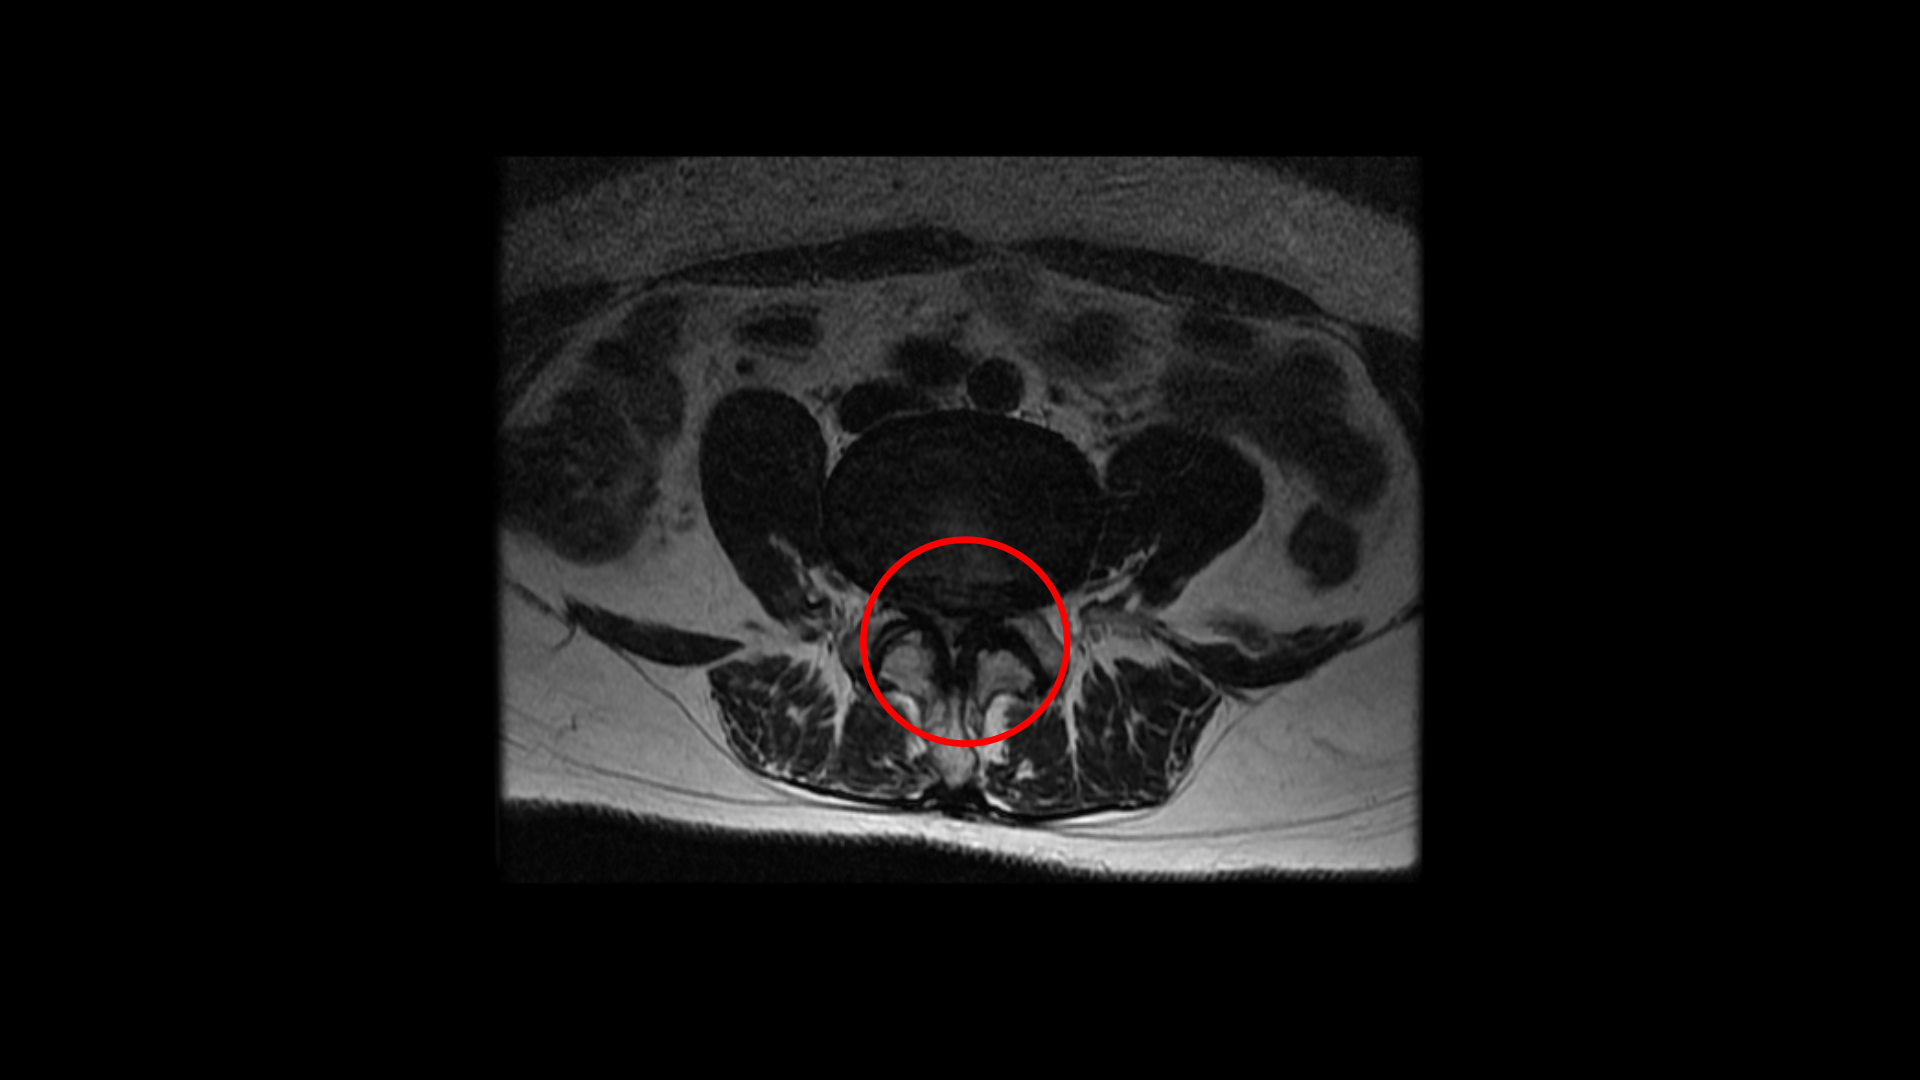

축상면에서 보면 흘러내린 수핵이 신경이 있어야 할 자리를 차지하고 있는 것이 보입니다.

또 보시다시피 이 4번 5번 마디에서는 심한 중심성 협착도 있습니다.